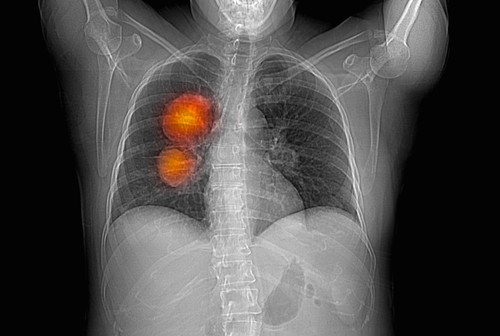

Prepoznavanje razlika između raka pluća kod pušača i nepušača od ključne je važnosti za uspešno lečenje. Naučnici su razvili personalizovane metode terapije koje su usmerene na specifične molekularne promene povezane sa rakom pluća kod nepušača.

Na primer, nepušači imaju veću verovatnoću da razviju adenokarcinom, vrstu raka pluća koja se takođe naziva sitnoćelijski rak pluća.

Ova vrsta raka karakteriše se sporijim rastom i može se prikazivati drugačije na medicinskim snimcima.

Grudni hirurg dr Danijel Bofa je razliku objasnio na sledeći način:

— Ako ste pušač, svoja pluća možete zamisliti kao vrećicu belih klikera, a rak je kao da tamo stavite crni kliker. Vrsta raka nepušača je više poput mrlje ili kvržice, više je kao maglovito područje.